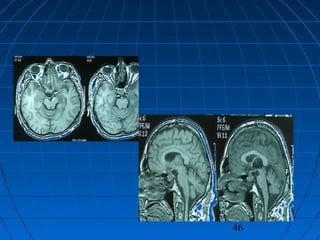

 56 yaşında erkek hasta56 yaşında erkek hasta

 BaşağrısıBaşağrısı (kronik-progresif, yaklaşık bir(kronik-progresif, yaklaşık bir

yıldır)yıldır)

 Nörolojik bakımdan normalNörolojik bakımdan normal

 Kranyal MRG:Kranyal MRG:

 pitüiter macroadenompitüiter macroadenom

 insidental AComA anevrizmasıinsidental AComA anevrizması

CERRAHİCERRAHİ

 Sol pterional trans-sylvian yaklaşımSol pterional trans-sylvian yaklaşım

 AcomA Anevrizması kliplendiAcomA Anevrizması kliplendi